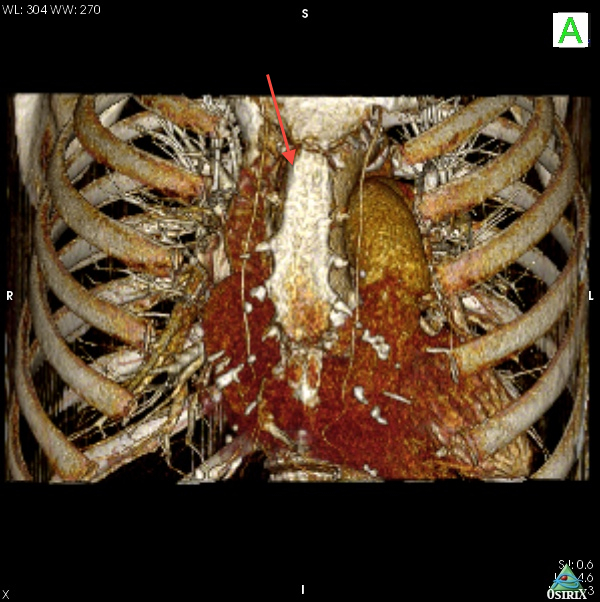

Fig. 6A: Case 2. In comparison to Case 1, the ascending aorta is more horizontal, and right-sided relative to the sternum. It was possible in this case to find a suitable puncture site at about 8 cm from the aortic annulus.

Fig. 6B: Case 2. The 3D volume rendering images revealed the right-sided and horizontal anatomy of the ascending aorta; this suggested that the optimal incision was a right upper mini-thoracotomy approach through the 2nd intercostal space.